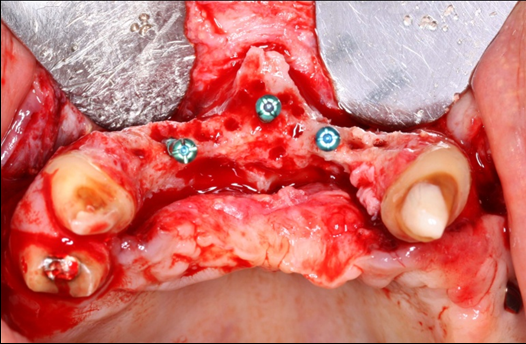

The surgical procedure was done under intravenous sedation using Fentanyl and Versed. Local anesthetic was used and a supra-crestal horizontal incision made on the palatal aspect of the anterior maxilla. A mucoperiosteal flaps were elevated, exposing a severely resorbed ridge of the pre-maxilla (Figure 2). Decortication was conducted with a round carbide bur in order to perforated the cortical aspect of the bone and expose the cancellous bone, to increase vascularity to the recipient site. Three screws were fixed parallel to the adjacent teeth, serving as “tent pole”. The screws had 14 mm length and approximately 6-8 mm of the tenting screws were exposed to the oral cavity (Figure 3). An absorbable collagen sponge (ACS) carrier/matrix was embedded with 12 mg of rhBMP-2 at 1.5 mg/mL (Infuse® Medtronic Sofamor Danek, Memphis, TN, USA) and allowed to absorb for approximately 20 min. The rhBMP-2/ACS was cut into strips, half of the strips were added to the natural bone mineral component derived from bovine bone (Geistlich Bio-Oss® granules small - 0.25 to 1 mm, Geistlich Pharma, Germany). Initially, some strips of rhBMP-2/ACS were placed over the buccal aspect of the residual alveolar ridge of the pre-maxilla, followed by strips mixed with bovine bone (Figure 4). The three screws were fully covered by rhBMP-2/ACS strips. Finally, a titanium mesh was adapted over the entire rhBMP-2/ACS graft and fixed with 2 monocortical screws, one on the buccal aspect and one on the palatal aspect of the ridge, respecting a 2 mm distance from the mesh to the adjacent teeth (Figure 5). Extensive undermining incision was conducted on the apical aspect of the buccal flap in order to achieve primary closure.

Figure 2.Occlusal view of the pre-maxilla after elevation of amucoperiosteal flap. Noteright and left pre-maxilla buccal plate concavities due to severely resorbed ridge. The central tenting screw is located mid-way into the nasal spine.